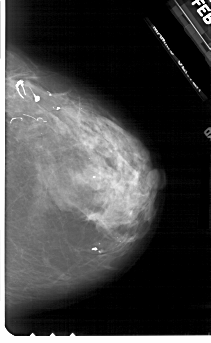

A_1930_1.RIGHT_MLO

RIGHT_MLO LINES 5491 PIXELS_PER_LINE 3316 BITS_PER_PIXEL 12 RESOLUTION 43.5 NON_OVERLAY